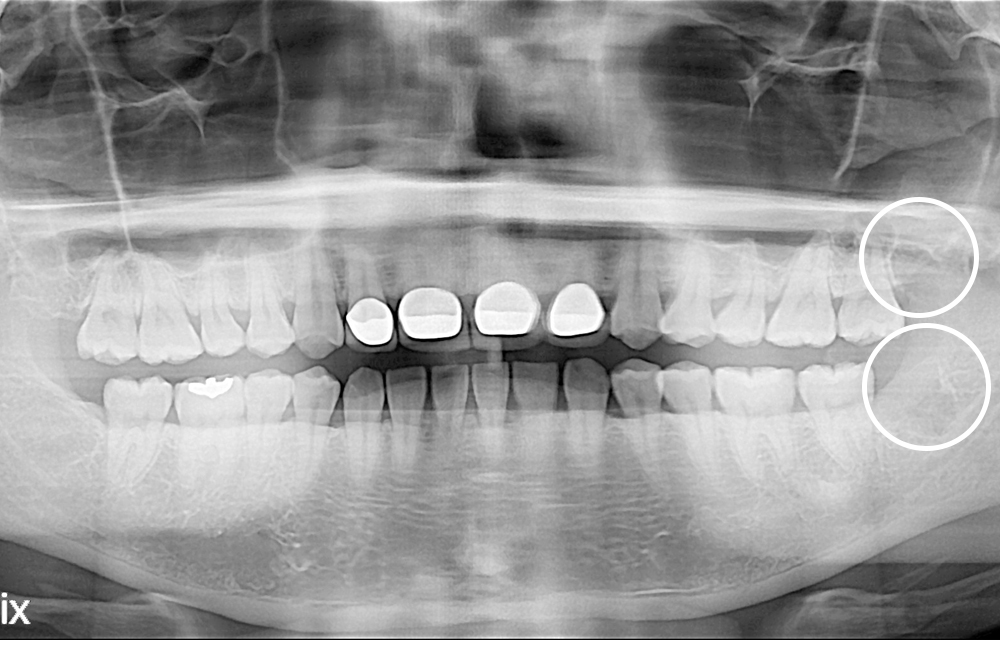

[사랑니] 매복 사랑니 발치

치료후 : 2020-03-04

세종치과는 구강악안면외과학 박사이신 원장님이 발치하는 치과입니다.